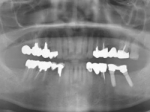

ショートインプラント

術前術前骨の高さが不足している場合、通常のインプラントでは処置が不可能なものが多い。特殊なショートインプラントを用いて可能になる例。 術前 術前CT像術前CT像術前CT像、下歯槽神経が下あごの中央部を走行しているため利用できる骨の高さが少ない。 埋入予定計画埋入予定計画埋入予定計画 術後レントゲン術後レントゲン、ひだりは少し神経をおそれすぎてやや埋入深度が不足、しかしこれでもしっかりと骨と固着した。

上部装着後のレントゲン像上部装着後のレントゲン像上部装着後のレントゲン像 術前口腔内写真術前口腔内写真術前口腔内写真 術後口腔内写真術後口腔内写真術後口腔内写真、食事がおいしくなったと非常に満足されている。